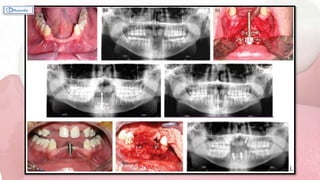

SYNONYMS: Socket Shield Technique; Partial Extraction Therapy; Root Submergence Technique

ROOT MEMBRANE TECHNIQUE

Reference: Chappuis V, Araujo J et al; 2017

For preserving the buccal bone with up to 10 -

year follow-up is the in-situ maintenance of the

buccal portion of the root in a procedure.

Hypothesis: By maintaining the buccal aspect of

the root and its associated periodontal ligament

(and hence the associated blood vessels), one may

be capable of preventing the physiologic bone

resorption of the buccal bone.

Reference: Hürzeler MB, Zuhr O, Schupbach P, Rebele SF, Emmanouilidis N, Fickl S. The

socket-shield technique: A proof-of-principle report. J Clin Periodontol 2010;37:855–862.